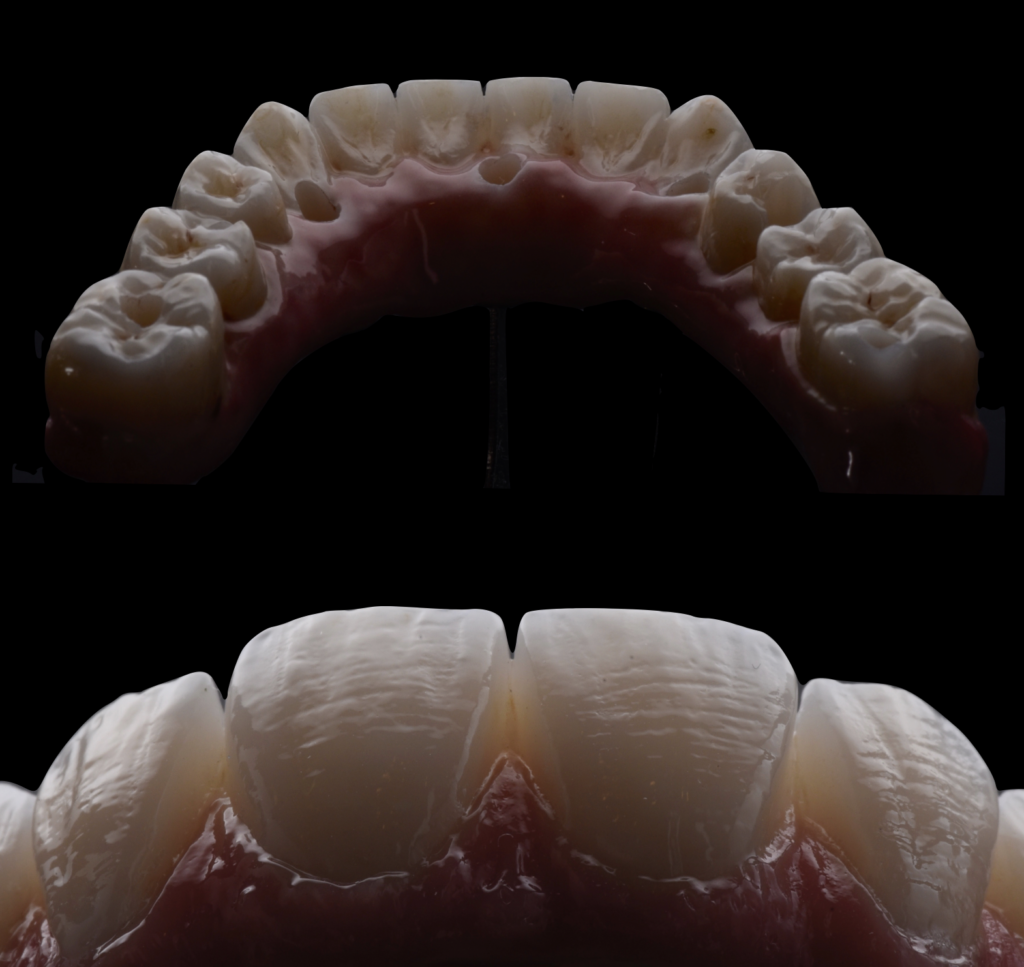

Paciente siempre había tenido mucho miedo al dentista, por lo que le propusimos proceder con la cirugía bajo sedación consciente, para que el paciente estuviera tranquilo y no recordara nada después de despertarse de la cirugía. El paciente aceptó, así que realicé la cirugía con anestesia y sedación consciente, y la cirugía salió muy bien, lo que nos permitió tomar medidas el mismo día y hacer una carga inmediata, evitando que el paciente estuviera sin dientes en ningún momento. Una vez que los implantes se habían cicatrizado, tomamos medidas para la prótesis definitiva, que en este caso fue hecha de circonio. El paciente está feliz con su sonrisa, pero sobre todo comenta que ahora puede comer con alegría.